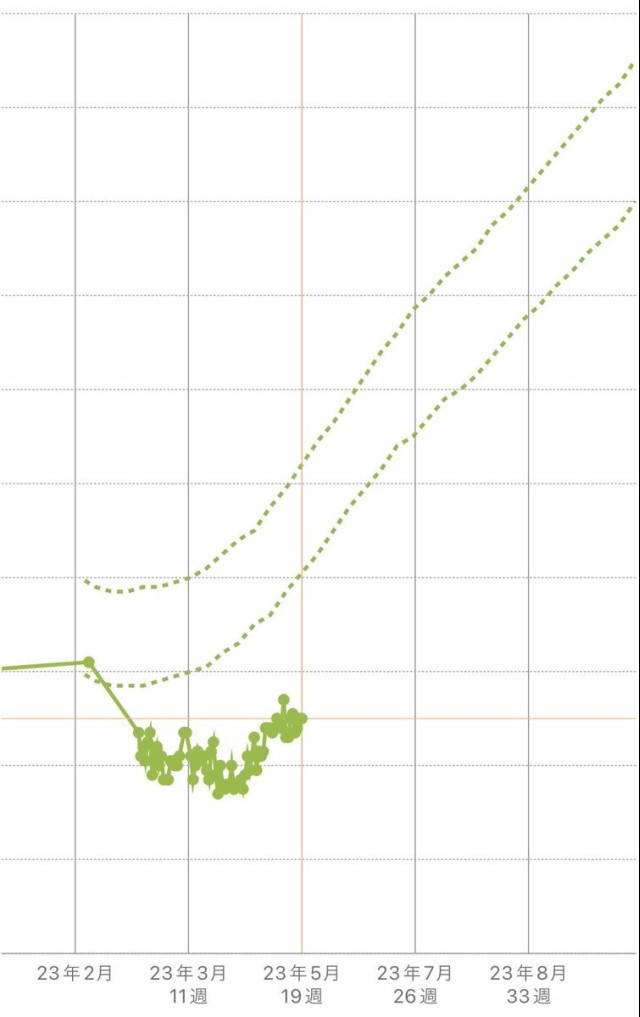

体重管理 カレンダーに書くだけで、ずっとサボってた体重入力。やっとアプリに入れた〜! まともに体重をつけていなかった妊娠初期にガクッと減ったけど、最近は順調に増えてる⭕️

体重管理 32wでやっと!つわりで減った分を取り戻して妊娠前体重に戻った?長かった